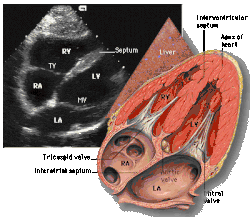

![]() Subcostal four chamber |

Each figure contains a TTE with a black background, and a corresponding colored illustration. | Patrick J. Lynch and C. Carl Jaffe, Yale University, 2006. | ||||||||||

Click on a figure to enlarge it and see some parts of the heart identified. RV, right ventricle; LV, left ventricle; RA, right atrium; LA, left atrium; TV, tricuspid valve; MV, mitral valve; AV, aortic valve; RVOT, right ventricular outflow tract; LVOT, left ventricular outflow tract |